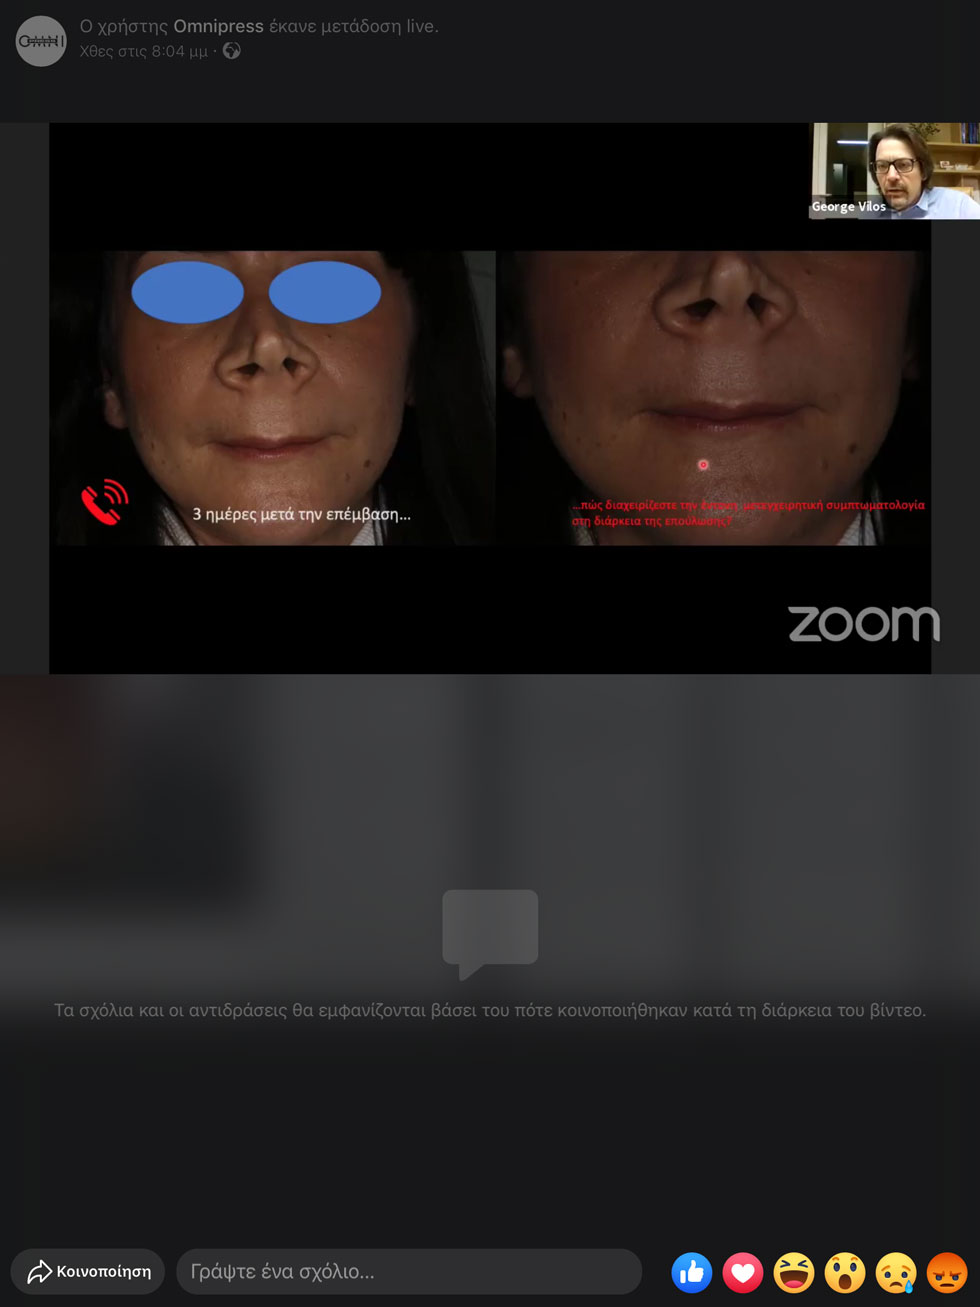

Σάββατο βράδυ, 11.04.2020: Είμασταν σπίτι και συναντηθήκαμε στις 20:00 μέσω zoom και Facebook live για να παρακολουθήσουμε τρεις από τους πιο έμπειρους, στην ειδικότητα τους οδοντιάτρους, τον περιοδοντολόγο Γεώργιο Γούμενο, τον γναθοχειρουργό Γιώργο Βήλο και τον προσθετολόγο Σταύρο Πελεκάνο να συζητούν και να σχολιάζουν live το σχέδιο θεραπείας ενός κλινικού περιστατικού του Γεώργιου Γούμενου, το οποίο αφορούσε την αισθητική ζώνη και παρουσίασε ο ίδιος στο webinar.

Πρόκειται για την περίπτωση μιας γυναίκας 38 ετών με χρόνια γενικευμένη περιοδοντίτιδα μετρίας βαρύτητας με εντοπισμένες περιοχές προχωρημένης #26,47 (Εικ.1), ελεύθερο ιατρικό ιστορικό, μη καπνίστρια, η οποία προσήλθε στο ιατρείο θέλοντας να φτιάξει το χαμόγελο της[1].

Ο Γεώργιος Γούμενος παρουσίασε βήμα βήμα φωτογραφίες και εξηγώντας ταυτόχρονα σε όσους συμμετείχαν στο webinar πώς και γιατί οδηγήθηκε σε αυτές τις επιλογές. Η διάρκεια του webinar ήταν κοντά στις 3 ώρες, μιας και… το πάθος για την οδοντιατρική δεν περιορίζεται!

Τo σχέδιo θεραπείας που ακολούθησε ο Γεώργιος Γούμενος, σχολίαζαν οι άλλοι δύο συμμετέχοντες, Γιώργος Βήλος και Σταύρος Πελεκάνος, βλέποντας το για πρώτη φορά χτες στο webinar, όπως δηλαδή συμβαίνει και στην πραγματικότητα όταν οι οδοντίατροι ανταλλάσσουν μεταξύ τους απόψεις.